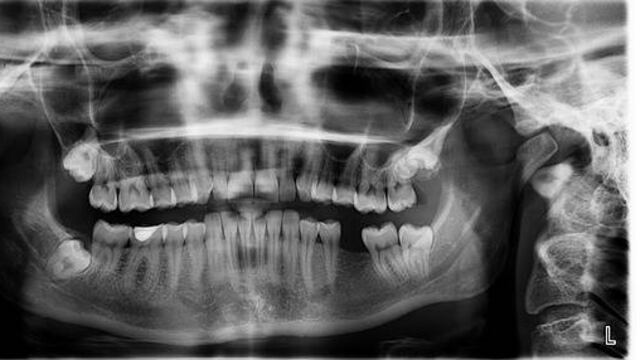

Y es que según informa el New India Express, los doctores ordenaron realizarle al niño una radiografía y una tomografía computarizada para encontrar el problema, y fue allí cuando notaron algo increíble: el paciente tenía más de 500 dientes en su boca.

Exactamente, el niño tenía 526 dientes.

Por su parte, el académico de cirugía oral y maxilofacial, P. Senthilnathan, explicó que el pequeño tenía una "estructura en forma de bolsa" en la boca, padecimiento que se conoce como odontoma compuesto.

"El crecimiento similar a un tumor impidió el crecimiento permanente de los molares del lado afectado", explicó el especialista.

"La radiografía y la tomografía computarizada mostraron múltiples dientes rudimentarios en un tejido similar a una bolsa".